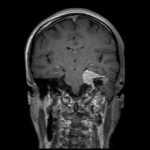

No.’25_107 手術前1

No.’25_107 手術前2